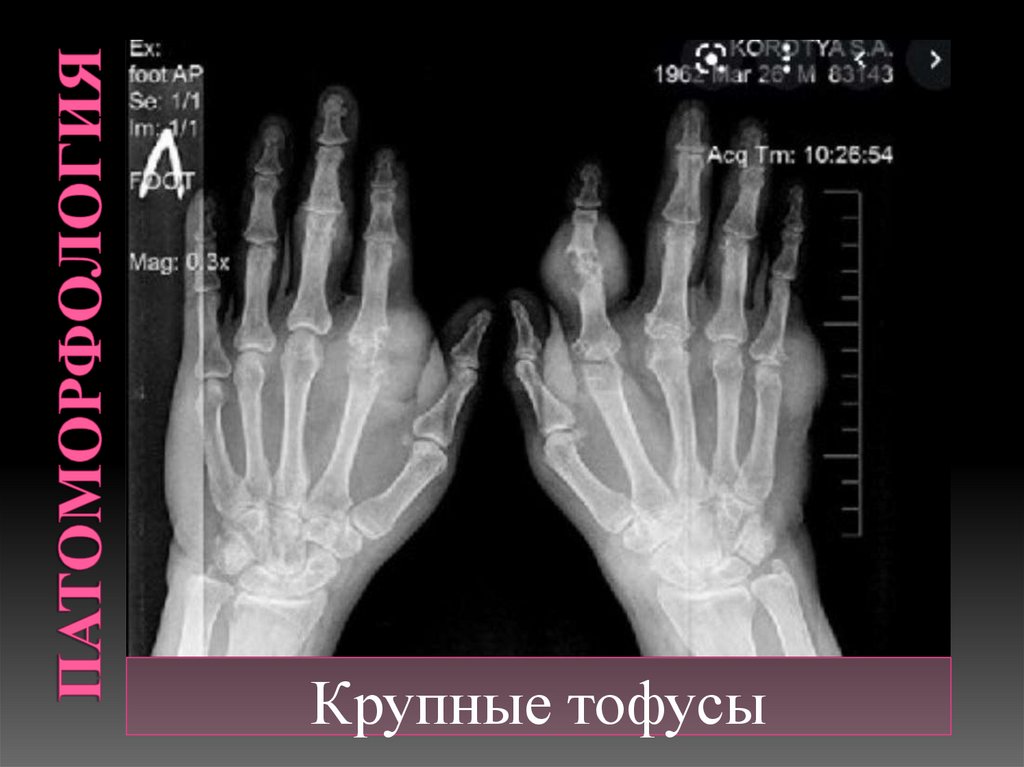

Крупные тофусы

Тофус (лат. tofus — пористый камень)

— общее название очагов

патологического уплотнения

подкожной клетчатки.

Большое скопление кристаллов уратов,

окруженное гранулематозной тканью.

Тофусы со временем кальцифицируются

и оссифицируются.